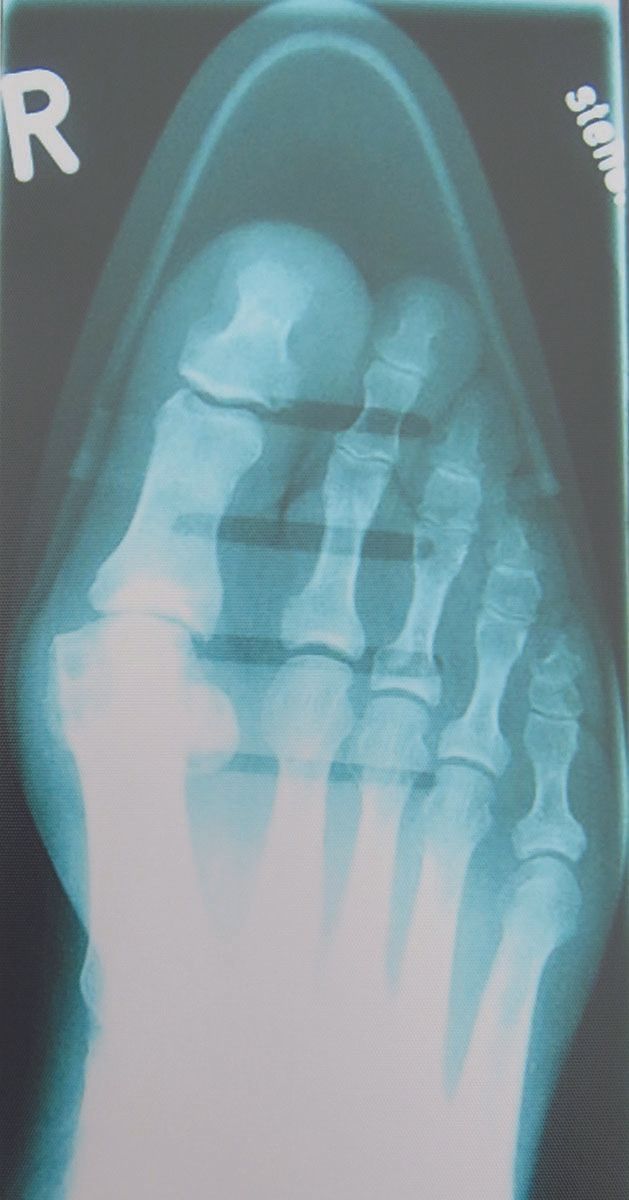

Mise au point Le syndrome de la chaussure de Cendrillon , Harald Kuhn St. Franziskus Hospital Lohne, Lohne, Allemagne N°280 - Janvier 2019 ● 13 min de lecture